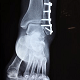

Recall from lesson 1 that you are working for a company that makes small specimen cabinet x-ray machines for medical research. Today you will learn how to do some calculations with the data that you might collect from such a machine.

The basic equations for dual-photon absorptiometry can be derived from a number of underlying assumptions. First, it is assumed that the material is composed of varying amounts of only two substances (in this case bone and soft tissue). Second, it is assumed that scatter can be ignored. Under these circumstances, for any given photon energy, the number of photons striking the detector (N) can be calculated from the number of incident photons (No) using Beer's law.

where μs and μb represent the mass attenuation coefficients (cm2/g) of soft tissue and bone (respectively) and Ms and Mb represent the area densities (g/cm2) of the two tissue types.

I = I o e -μl

I = Intensity.

I0 = Intensity with no object.

μ = attenuation coefficient (depends upon material and x-ray energy).

l = length of the x-ray path.